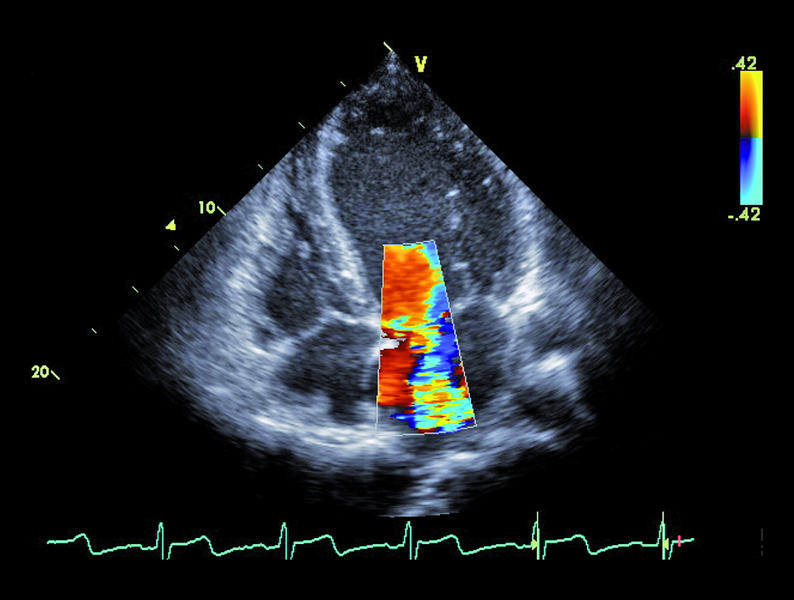

Infekcyjne zapalenie wsierdzia z zajęciem obu natywnych zastawek serca lewego nie budzi w tym przypadku wątpliwości. Proces zapalny może być rozpoznany echokardiograficznie na podstawie linijnych ech mogących odpowiadać rozerwanemu płatkowi zastawki aortalnej oraz na podstawie ciężkiego wypadania płatka zastawki mitralnej (flail), mającego zapewne charakter poinfekcyjny (ryc. 1). Stopień destrukcji zastawki mitralnej w porównaniu z zastawką aortalną wydaje się większy. Między segmentami A2 i P3 pojawia się tętniakowate uwypuklenie, będące pozostałością nacieczenia zapalnego i martwicy tkanki (ryc. 2). Tryb kolorowego doplera ujawnia dwa strumienie niedomykalności – jeden, ekscentryczny wynikający z wypadania przedniego płatka i biegnący wzdłuż bocznej ściany przedsionka (ryc. 3), i drugi pojawiający się w pewnej odległości od miejsca koaptacji, w miejscu, w którym fali zwrotnej trudno się spodziewać, jeśli struktura tkanki budującej płatek jest nienaruszona (ryc. 3, 4). Strumień niedomykalności mitralnej ma w tym wypadku charakter ostry i trafia do nieprzygotowanej i niepowiększonej jamy lewego przedsionka (ryc. 3, 4). Umiarkowana dotychczas niedomykalność aortalna, którą chory przez wiele lat dobrze tolerował, się nasiliła. Dowodem na to jest krótki czas spadku gradientu ciśnień aorta – lewa komora (poniżej 200 ms) (ryc. 5) oraz wyraźny sygnał wsteczny holodiastoliczny w aorcie zstępującej, świadczący o wysokiej wartości frakcji niedomykalności aortalnej (iloraz całki prędkości wypływu krwi na obwód i prędkości fali wstecznej 83%!) (ryc. 6).